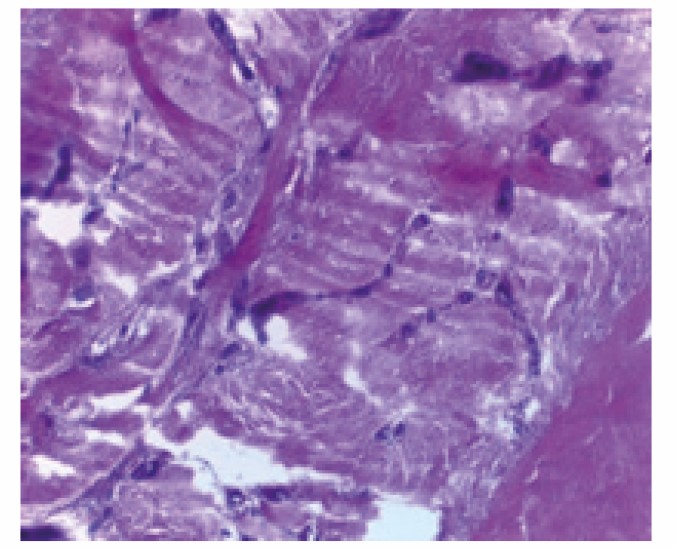

Гистологическое исследование костной ткани крыс I и II группы после лечения представлены на рисунках 1 и 2 (см. 2-ю стр. обложки). На фрагментах нижней челюсти животных, прослеживается положительная динамика восстановления костной ткани. Это проявляется в отсутствии остеокластов, уменьшении лакун, уплотнении и нормализации структуры ткани. Кроме того, наблюдается восстановление микроциркуляторного русла, формирование сосудов и грануляционной ткани.

Рисунок 1. Структура костной ткани фрагмента нижней челюсти крысы после иммунотропной композиции без витамина D3

Примечание. Окраска гематоксилином и эозином, увеличение в 400 раз.

Figure 1. Structure of the bone tissue of a fragment of the lower jaw of a rat after an immunotropic composition without vitamin D3

Note. Hematoxylin and eosin staining, 400× magnification.